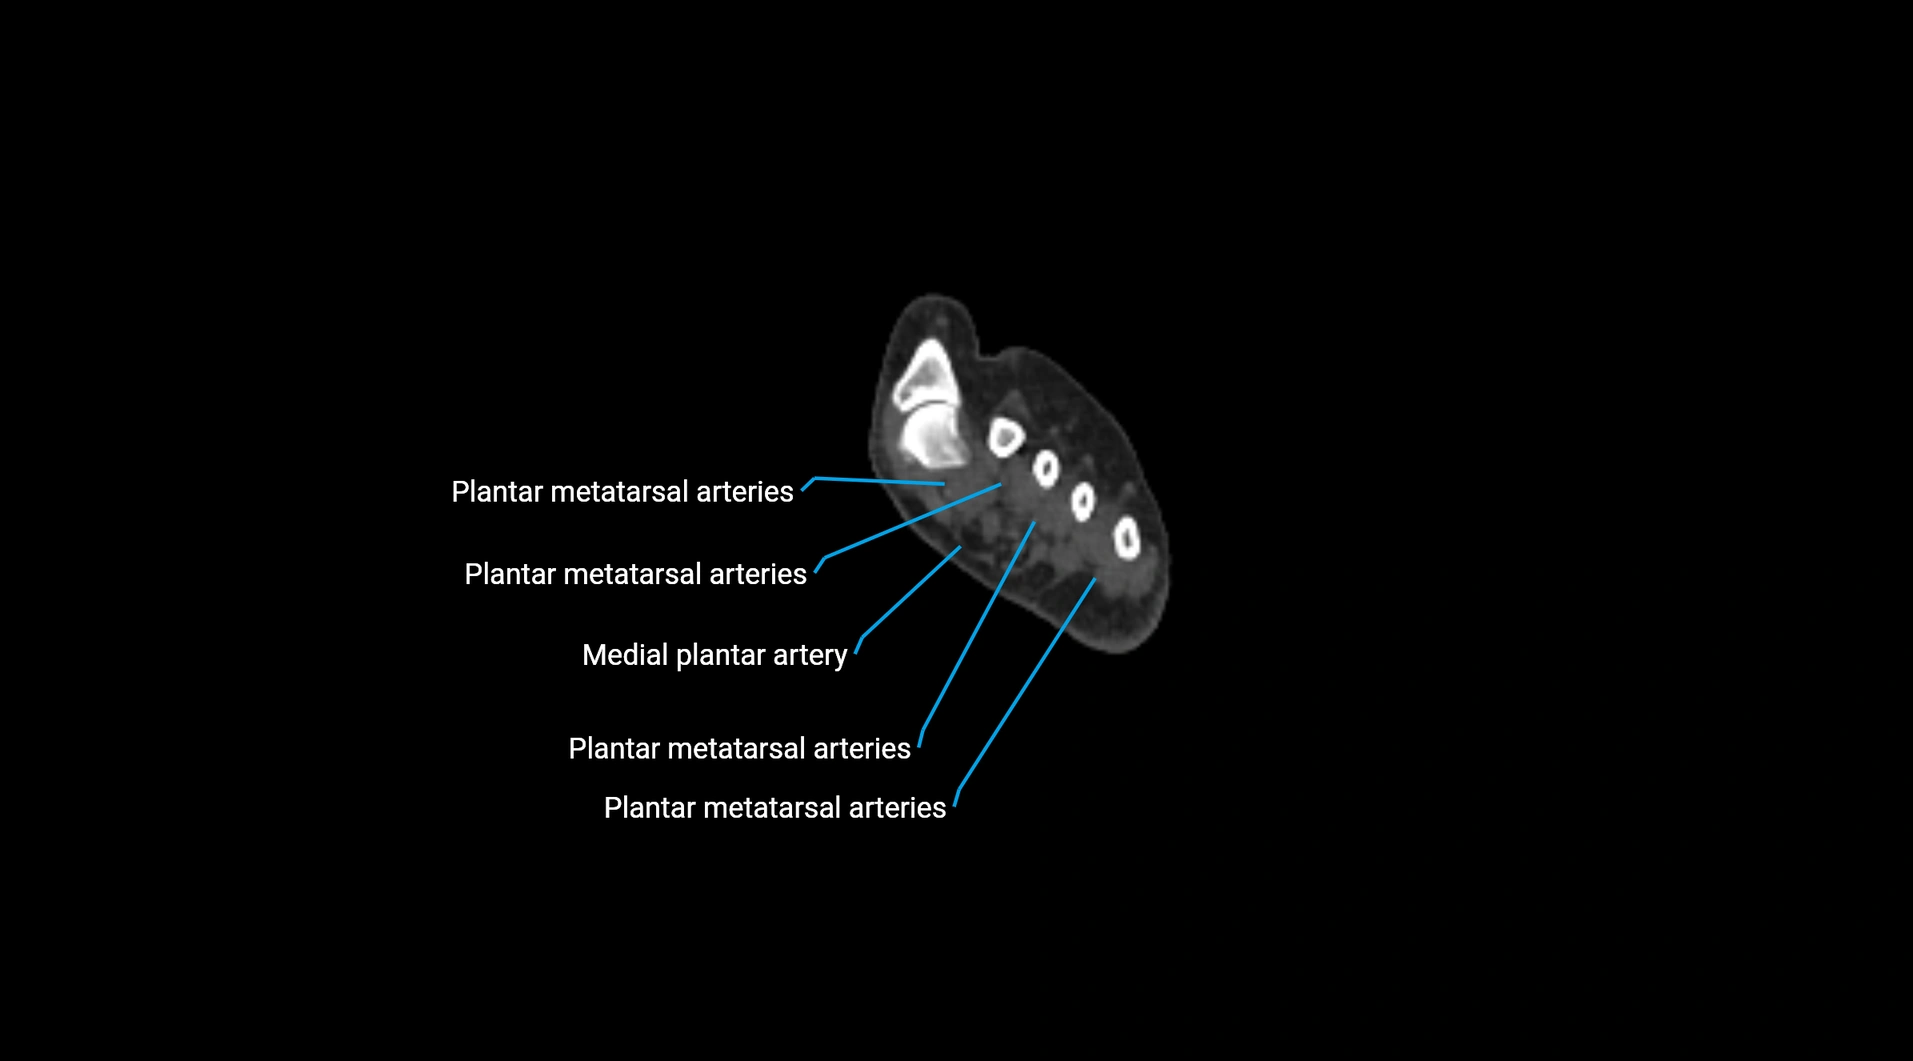

CT images

image

Contrast-enhanced CT (CTA):

• Gold standard for abdominal aortic imaging

• Provides excellent detail of lumen, wall, aneurysm, thrombus, and branch vessels

• Multiplanar and 3D reconstructions help in aneurysm measurement, stent graft planning, and dissection evaluation